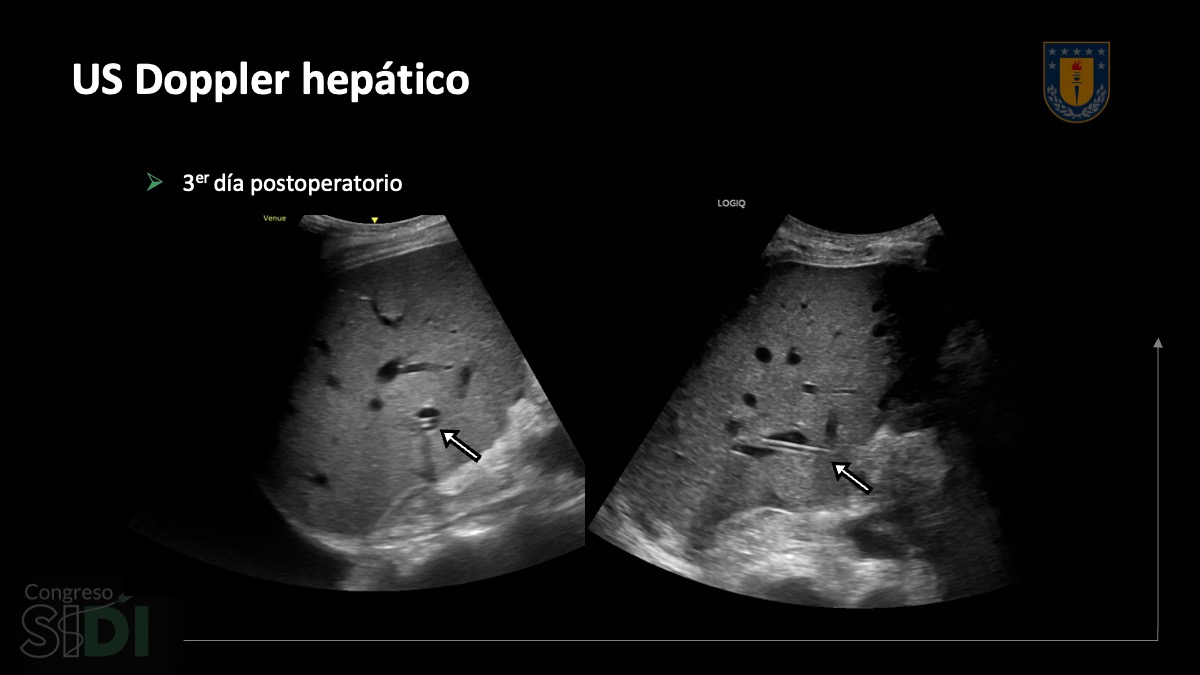

SIDI25_PE_014_Cristian Lindner_03